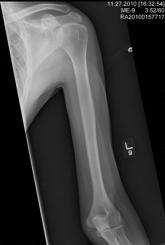

Shoulder Pain in Man Hospitalized for Brain Mass

- Author:

- Nandan Hichkad, PA-C, MMSc

Publish date: January 1, 2011